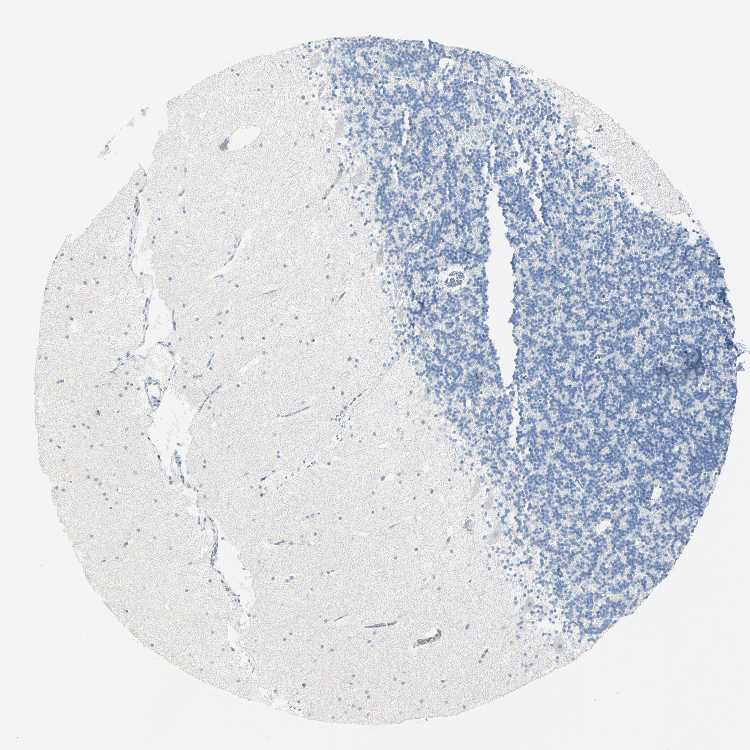

CEREBELLUM - Antibody stainingi

Antibody staining in the annotated cell types in the current human tissue is reported as not detected, low, medium, or high, based on conventional immunohistochemistry profiling in selected tissues. This score is based on the combination of the staining intensity and fraction of stained cells.

Each image is clickable and will lead to virtual microscopy that enables deeper exploration of all samples and also displays staining intensity scores, fraction scores and subcellular localization as well as patient and tissue information for each sample.

Antibody HPA015794Antibody CAB004544

Purkinje cells Not detectedNot detected

Cells in granular layer Not detectedNot detected

Cells in molecular layer MediumNot detected